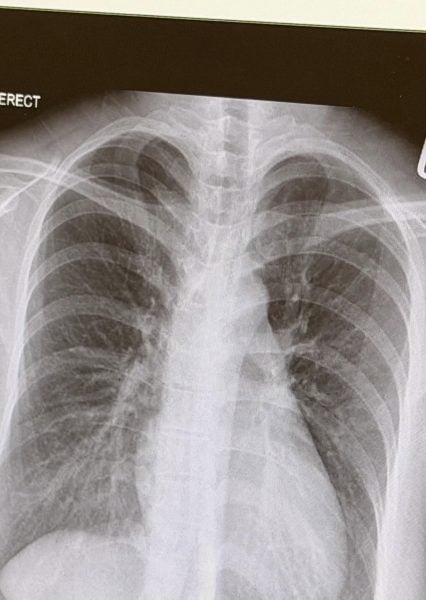

X-ray reveals white streaks inside lungs

The scan revealed white streaks across her lungs, a sign of bacterial infection.